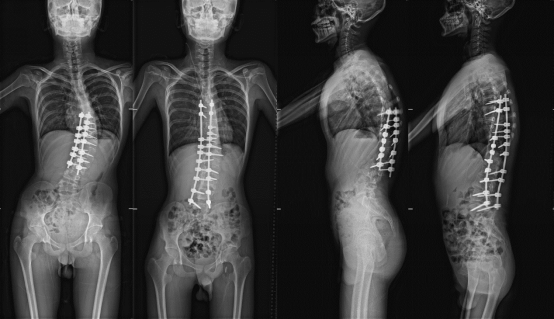

历时五年,经历两次矫正手术、更换四副硬质盔甲(支具)……福建省立医院骨科与运动医学中心徐杨教授团队8月9日最后一次对患者进行回访,意味着该中心接诊的这例早发先天性半椎体导致的脊柱侧弯手术正式获得成功。

“患者小杰(化名)是一个比较典型的先天性脊柱侧弯。”徐杨回忆,患者第一次就诊是在2019年3月,当时他还不到10岁。由于发现太晚,外观的畸形已经非常严重,对他的心肺功能也产生了影响,如拖延手术,畸形会进一步加重到难以解决的程度。由于孩子还没进入到第二个快速发育期(青春期),手术矫正后随着孩子的进一步生长,畸形还是有再次加重的可能。

徐杨团队根据检查影像作了详实的分析和评估,决定将患者的T12半椎体切除,以较短节段固定进行畸形矫正。术后早期效果良好,患者身高由术前的1.29米纠正到术后的1.37米,剃刀背畸形得到明显纠正。“孩子术手还需要持续佩戴支具和严密随访观察,等骨骼发育接近成熟的时候再次进行最终的融合手术。”徐杨说。

五年的持续跟踪治疗,更换了四副支具,随着孩子进入青春期,身高长到1.65米,畸形再次加重,支具治疗已经不能阻止畸形进展,出现了明显的躯干偏移。

“今年他已经15岁了,骨骼发育基本上接近到成熟状态,我们经过多学科会诊评估,觉得可以在这个时候给他做一次最终的手术,对整个畸形进行融合和固定,避免畸形进一步加重。”徐杨表示,第二次手术需要考量的因素很多,包括侧弯的柔韧性、脊柱和肩膀的整体平衡、融合固定的节段以及上次手术的疤痕组织等。

今年3月,福建省立医院骨科与运动医学中心为患者做了第二次手术,基本矫正了畸形,融合节段延长,术后身高达到1.73米。